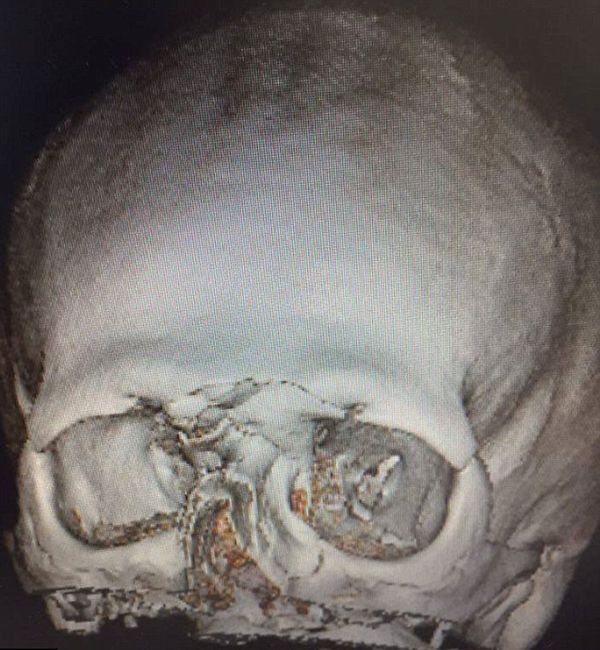

En total, se le fracturaron 15 huesos del rostro y el jugador publicó una imagen en las redes sociales para mostrar las secuelas en su cara, luego de publicar la radiografía de su cráneo.